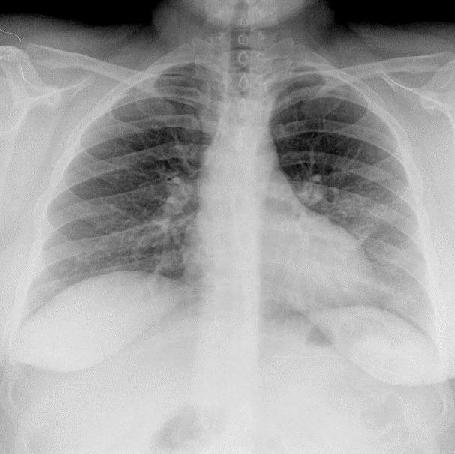

INSPIRATION

Poor Inspiration (picture to the right -->):

* False enlarged heart

* Difficult evaluation of the lungs

Same patient on inspiration (below):

|